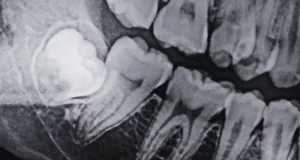

Can You Drink Alcohol After a Tooth Extraction? (9 Safety Tips)

No. You should not drink alcohol after a tooth extraction. The American Dental Association (ADA) recommends avoiding alcohol...